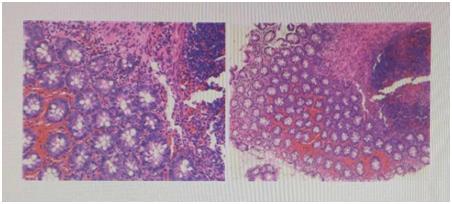

病理诊断——先天性巨结肠诊断的“金标准”!

“芝麻粒”大小直肠壁组织检查。